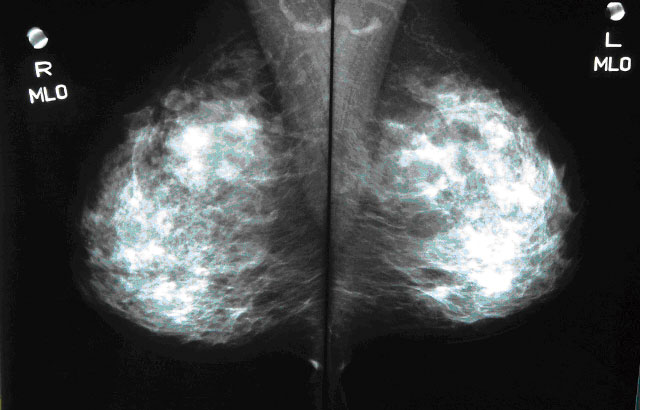

マンモグラフィ

乳がんや乳腺症を調べる検査です。40歳以上の方、肥満傾向の方や乳房が大きい方、授乳経験のない方、乳がん家族歴のある方にお勧めします。自分ではわからない小さなしこりや微細石灰化病変の発見、しこりの大きさ、浸潤の状況を調べます。

ペースメーカー、シリコンを挿入されている方は、検査をお受けになれません。

乳房検査セット

「マンモグラフィ」と「乳房超音波検査」をセットにしたお得なオプションです。乳がん検診を初めて受けられる方にお勧めします。